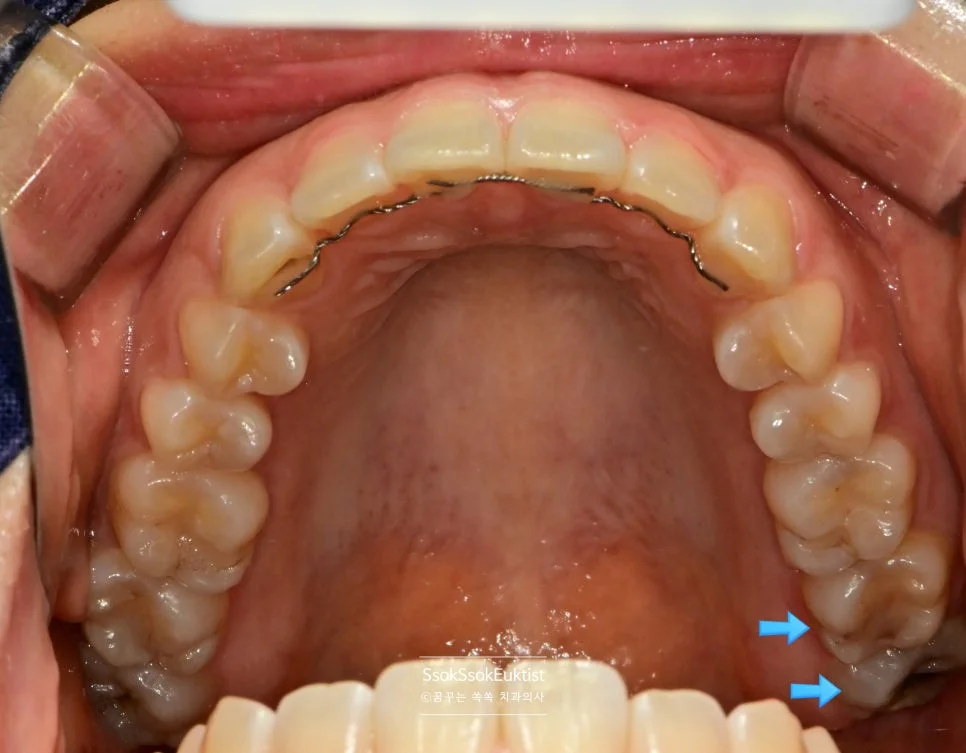

충치가 심하게 생긴 왼쪽 위아래 사랑니

충치가 심하게 생겨 사랑니 통증으로 오신 분인데요, 왼쪽 위아래 사랑니입니다.

바로 앞 치아는 멀쩡한데 왜 유독 사랑니만 충치가 있는 걸까요?

사랑니가 서로 닿아 기능하지 않기 때문입니다!

어금니의 씹는 과정(저작)은 어금니 머리를 세척, 청소하는 효과도 있는데요. 어금니가 서로 닿지 않으면 치아의 머리 면에 음식물이 계속 고여있으면서 충치가 생기게 됩니다!

예쁘게 1분 안에 발치하면 됩니다!